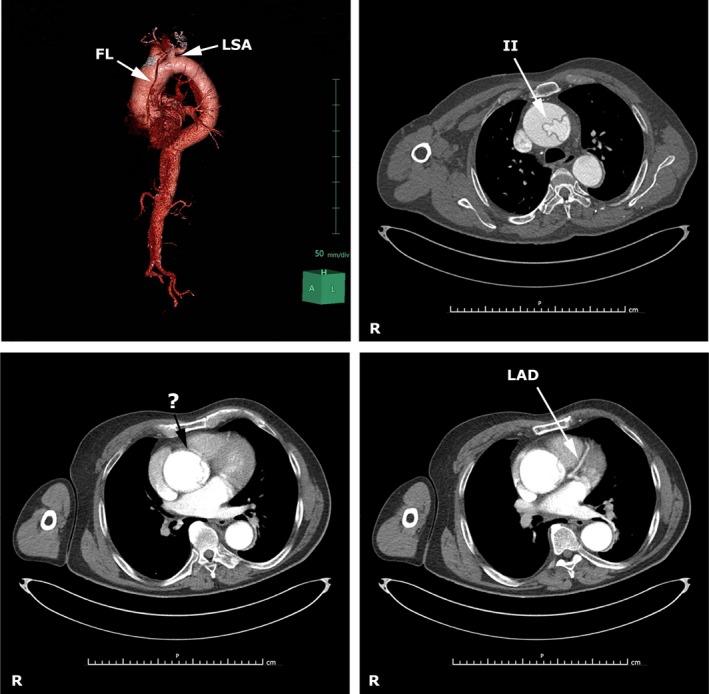

心房颤动,一种伴有疑似内膜-内膜套叠的急性斯坦福A型主动脉夹层的附带现象。

Atrial fibrillation, an epiphenomenon of acute Stanford type-A aortic dissection with suspected intimo-intimal intussusception.

Supraventricular arrhythmias can sometimes be "only" epiphenomena appearing during acute hypoxia, pneumonia, pulmonary embolism, and thrombosis. Indeed, atrial fibrillation is not rare in acute aortic dissection as it is estimated in about one half of patients and may be secondary to a perfusion deficit of the sinoatrial node artery.

室上性心律失常有时可能只是急性缺氧、肺炎、肺栓塞和血栓形成期间出现的“单纯”附带现象。事实上,急性主动脉夹层中房颤并不少见,据估计约一半患者会出现,且可能继发于窦房结动脉灌注不足。